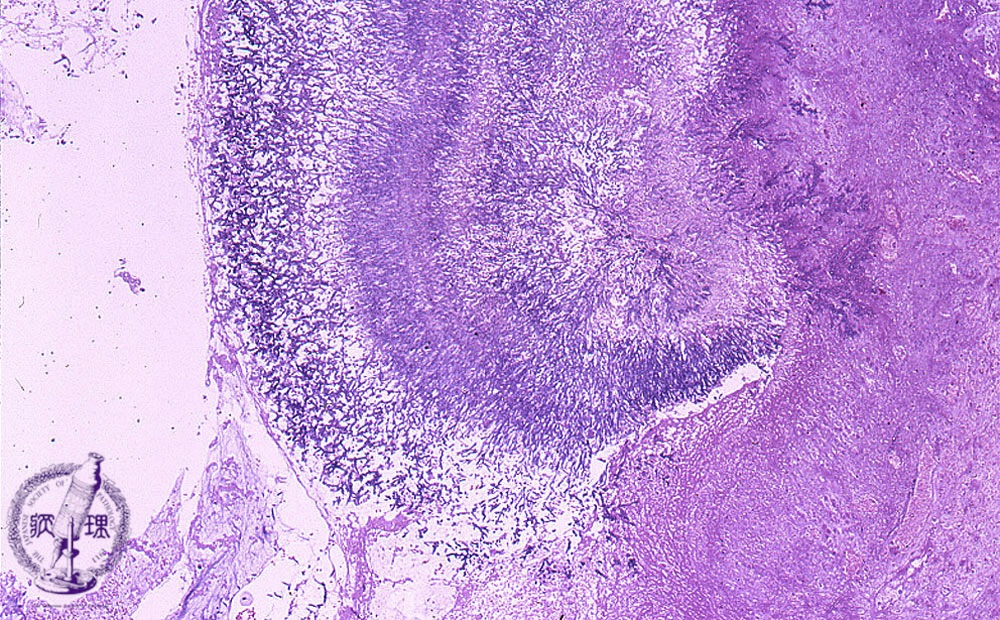

Microscopic view (HE stain, low power view): Hematoxylin stained aspergillus hyphae are septate, 3-11um in diameter and demonstrate Y-shaped branching at a roughly 45 degree angle, characteristics which help differentiate from other fungi.